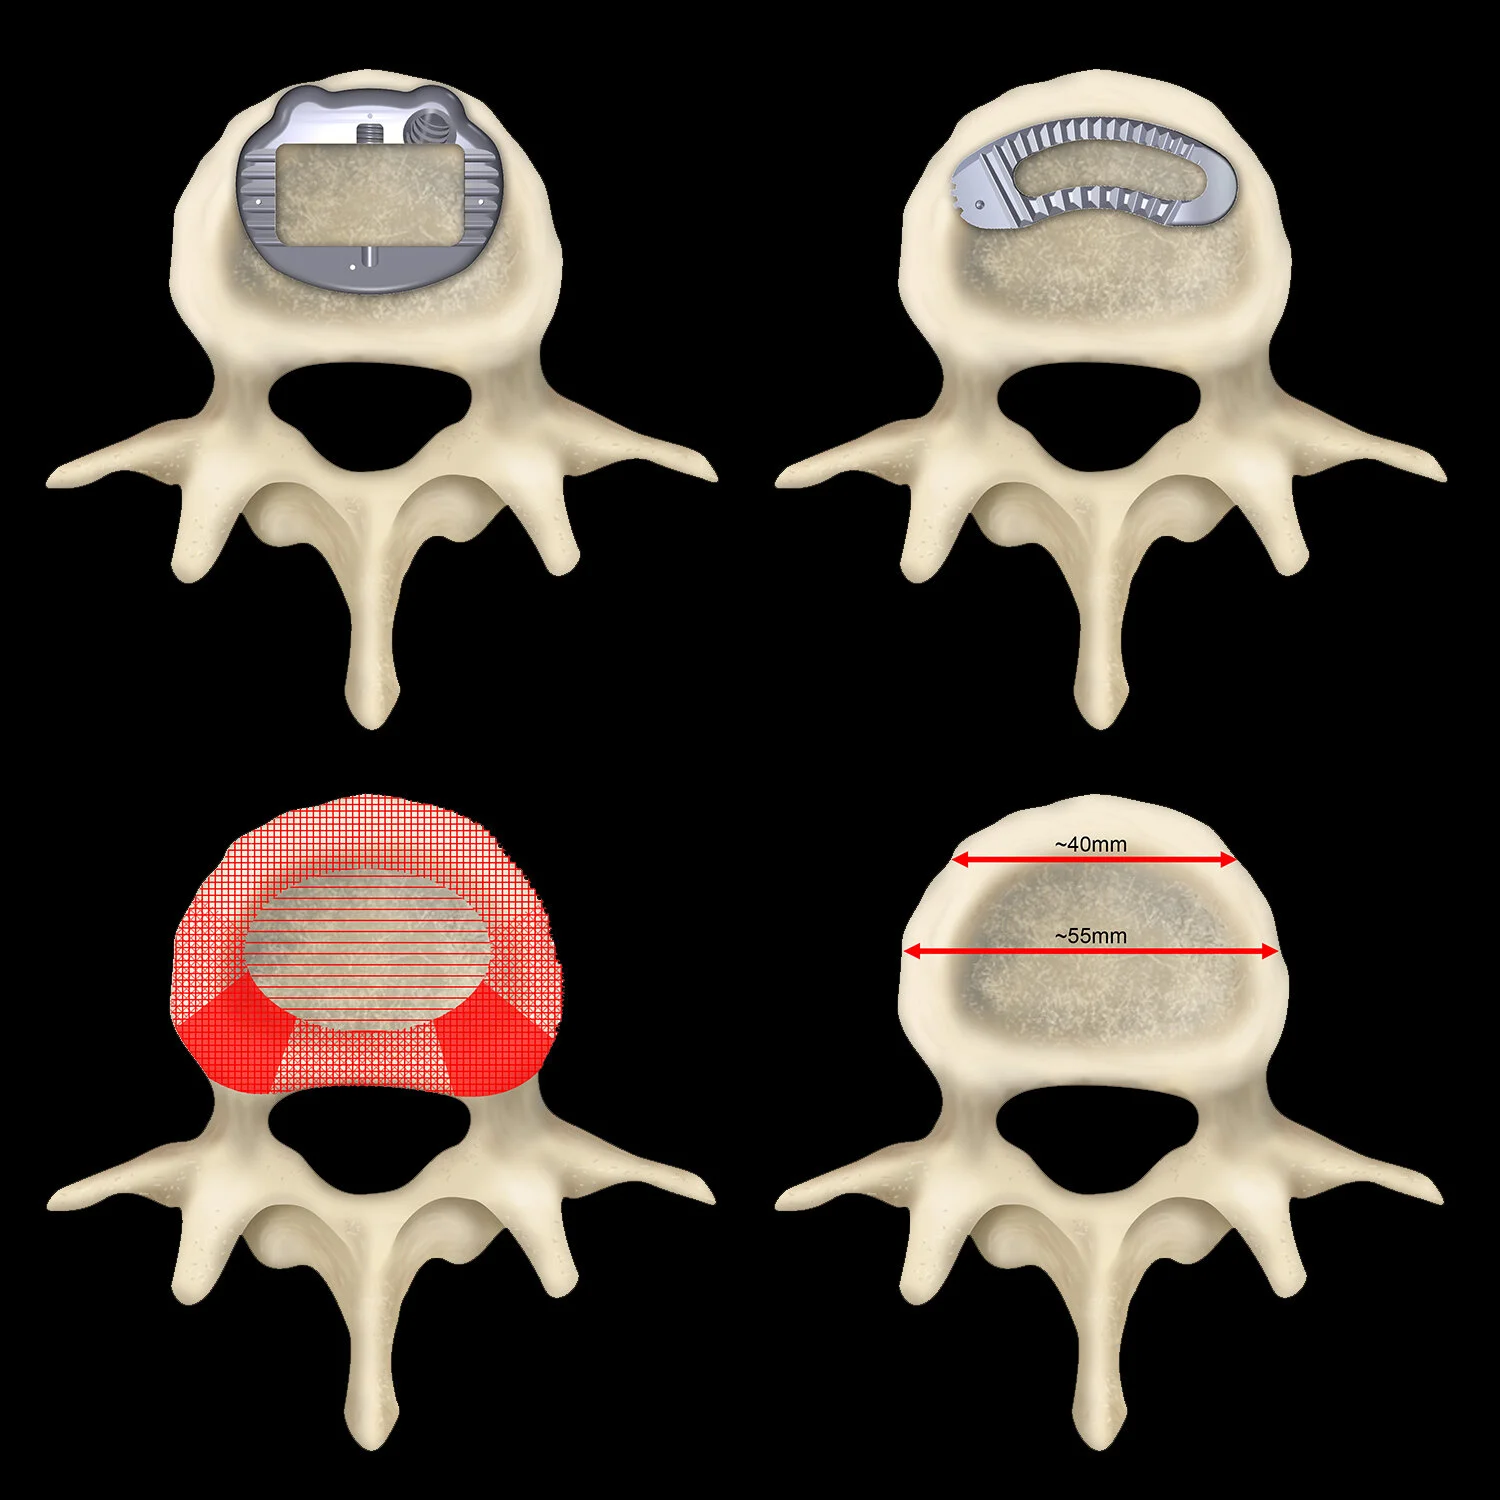

![Vertebral implants]()

Vertebral implants